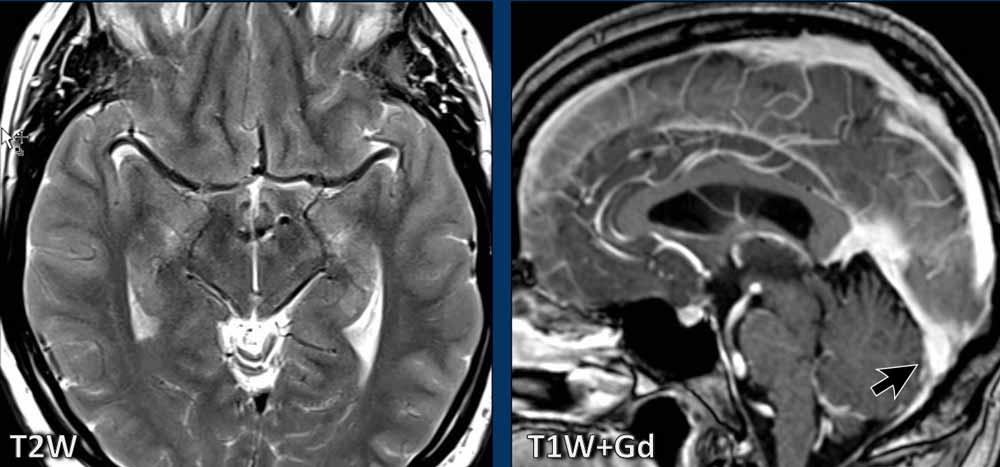

Hình ảnh

Trên MRI, có thể thấy rõ rằng các cấu trúc tăng tỷ trọng hai bên quan sát được trên CT chính là các động mạch não giữa.

Trên CT, do thiếu dịch não tủy xung quanh, các động mạch này có tỷ trọng cao hơn bình thường.

MRI cũng cho thấy hình ảnh trung não bị võng xuống, biểu hiện trên ảnh axial là hình dạng bất thường và trên ảnh sagittal là khoảng cách ngắn giữa thể vú và cầu não.

Có hình ảnh mặt dưới xoang ngang lồi ra.

Chúng ta có thể kết luận đây là một trường hợp SIH.